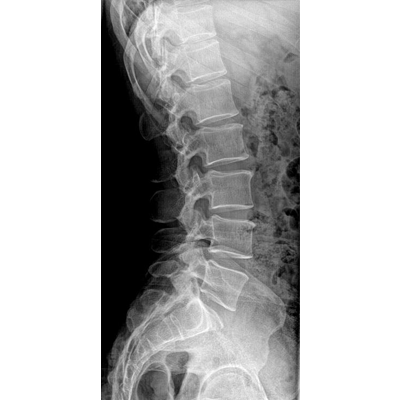

●大尺寸非晶硅平板探測器。

●探測器可以大范圍轉動,大尺寸有效探測面積,可滿足人體多部位攝影需求。